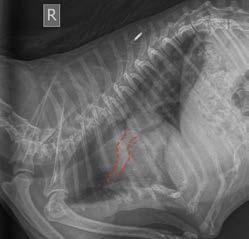

Conscious thoracic radiographs were taken, which highlight the very dilated and tortuous pulmonary lobar arteries in the lateral and dorsoventral views (credit to Dr Catheryn Walsh), consistent with heartworm infection. Cardiomegaly was appreciated; however, the left atrium did not appear obviously enlarged on radiographs and there was no obvious interstitial to alveolar pattern consistent with left-sided congestive heart failure.

Figure 4. Tortuous pulmonary artery on lateral view